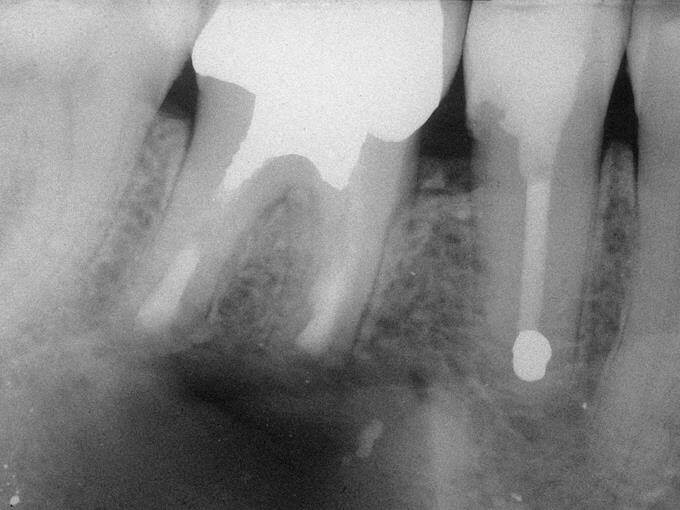

Endodontik müalicə (kanal müalicəsi) həyata keçirilən dişlərdə, kök kanallarının mürəkkəb konfiqurasiyası, yalnış və ya yetərsiz müalicə metodunun tətbiqi, bəzən də həkim səhvi/ehtiyatsızlığına bağlı olaraq təkrar iltihablanma – apikal ostit meydana çıxa bilir. Çox zaman bu tip iltihabi proseslər kliniki olaraq şikayətlərə səbəb olmadığından, zaman keçdikcə miqyasını genişləndirərək iltihab mənşəli odontogenik kistlərin yaranmasına gətirib çıxarır.

Bu zaman bəzi hallarda kanal müalicəsinin yenidən icrası (endodontik reviziya) mümkün olsa da, bir çox hallarda bu və ya digər səbəbdən həyata keçirilməsi mümkün olmur. Bu zaman əsas tətbiq edilən müalicə metodu dişi çəkməmək şərti ilə, iltihab ocağının uzaqlaşdırılmasını təmin edən – diş kökünün rezeksiyası metodudur. Bu əməliyyat vasitəsilə iltihab ocağı diş kökü ilə birlikdə kənarlaşdırılır və kök kanalları xüsusi metodla yenidən işlənir və doldurulur. Əməliyyat əsasən yerli ağrısızlaşdırma altında, xüsusi böyüdücü vasitənin tətbiqi ilə həyata keçirilir.